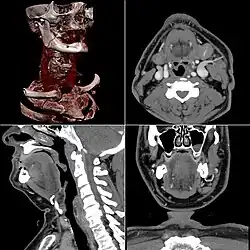

CT scan remains the cornerstone imaging modality for the initial evaluation and subsequent management of patients with acute traumatic brain injury due to its rapid acquisition time and high sensitivity for detecting hemorrhagic complications, such as intraparenchymal hematomas and subdural hemorrhages.[56] CT scan of the head is typically used to detect infarction (stroke), tumors, calcifications, haemorrhage.[57] Tumors can be detected by the swelling and anatomical distortion they cause, or by surrounding edema. CT scanning of the head is also used in CT-guided stereotactic surgery and radiosurgery for treatment of intracranial tumors, arteriovenous malformations, and other surgically treatable conditions using a device known as the N-localizer.[58][59][60][61][62][63]

Contrast CT is generally the initial study of choice for neck masses in adults.[64] CT of the thyroid plays an important role in the evaluation of thyroid cancer.[65] CT scan often incidentally finds thyroid abnormalities, and so is often the preferred investigation modality for thyroid abnormalities.[65]